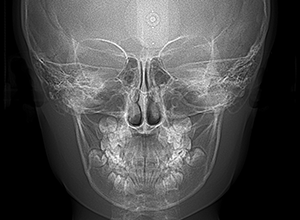

X-Ray

X-Ray所見

セファロ所見 SNAは84.3°、SNBは77.2°、ANBは7.1°とskeletal ClassⅡ、垂直的にはロウアングルの骨格形態をしていた。 上顎前歯は唇側傾斜を呈していた。

パノラマ所見 後継永久歯の歯数や萌出方向の異常は認められなかった。